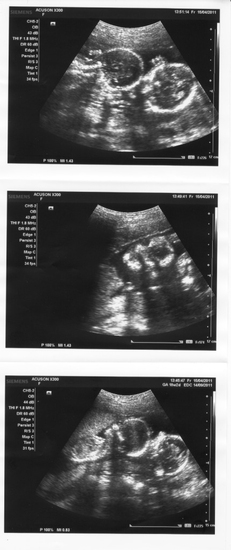

Сегодня пошли с мужем на Узи, нам 18 нед.2 дня - Дихориальная диаминотическая двойня - по развитию соответствуем сроку, всё хорошо, сделали даже фотографии =)

На первой фотке - две головы с машущими ручками;

На второй фотке - личико одного малыша;

На третьей фотке - как лежат два малышастика.